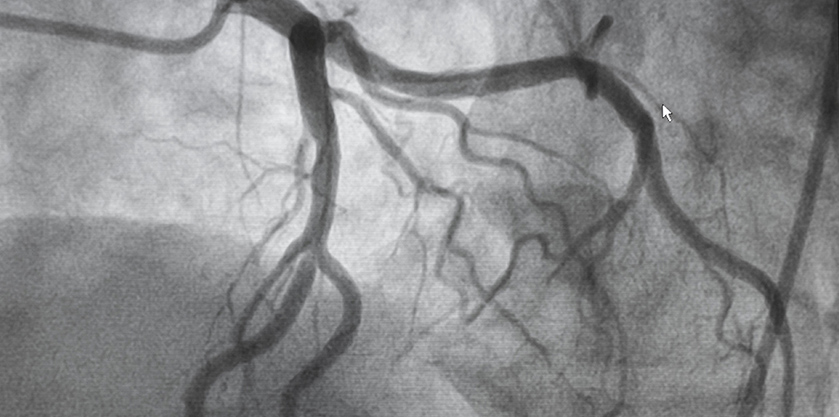

• Coronary Angiography: It is an invasive test performed in hospitals to look for narrowings or blockages in the blood vessels that supply the heart. If a narrowing or blockage of blood vessels is found that appears suitable, your cardiologist may proceed to perform angioplasty.